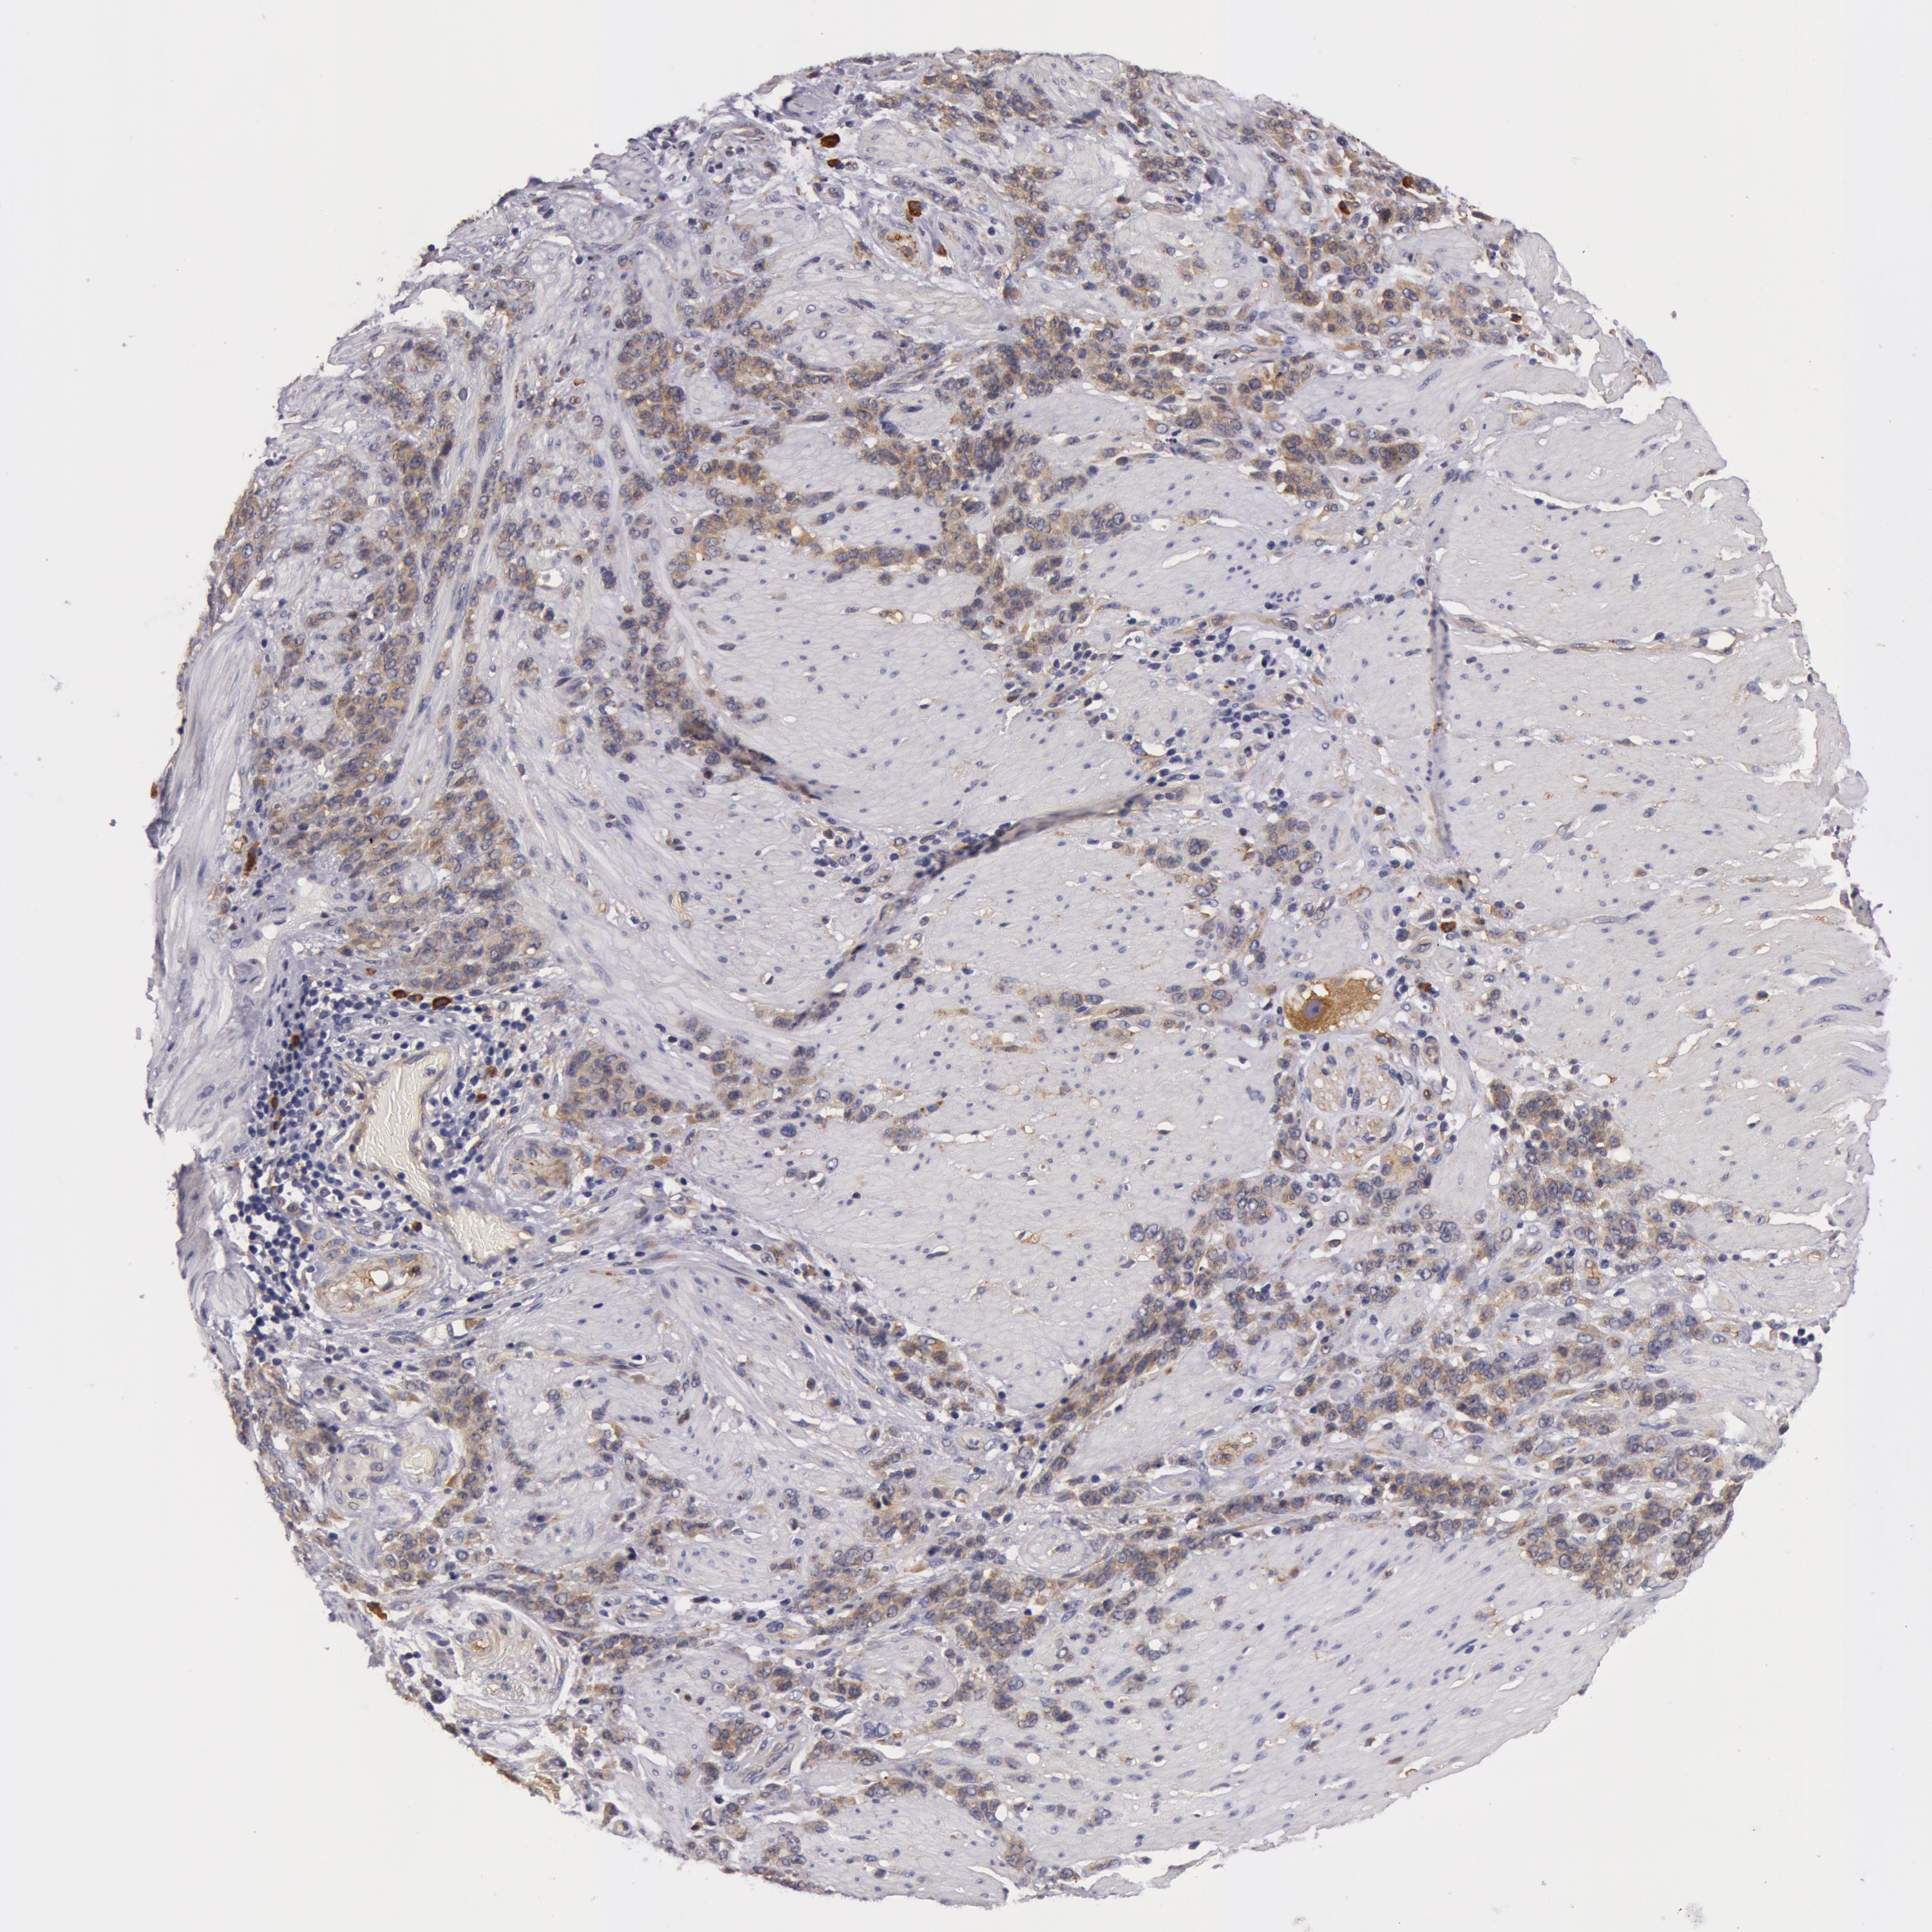

STOMACH CANCER - Protein expressioni

A mouse-over function shows sample information and annotation data. Click on an image to view it in a full screen mode. Samples can be filtered based on level of antibody staining by selecting one or several of the following categories: high, medium, low and not detected. The assay and annotation is described here.

Antibody stainingi

Antibody staining in the annotated cell types in the current human tissue is reported as not detected, low, medium, or high, based on conventional immunohistochemistry profiling in selected tissues. This score is based on the combination of the staining intensity and fraction of stained cells.

Each image is clickable and will lead to virtual microscopy that enables deeper exploration of all samples and also displays staining intensity scores, fraction scores and subcellular localization as well as patient and tissue information for each sample.

Antibody HPA001554

Staining

High

Medium

Low

Not detected

Intensity

Strong

Moderate

Weak

Negative

Quantity

>75%

75%-25%

<25%

None

Location

Nuclear

Cytoplasmic/membranous

Cytoplasmic/membranous,nuclear

Adenocarcinoma, NOS